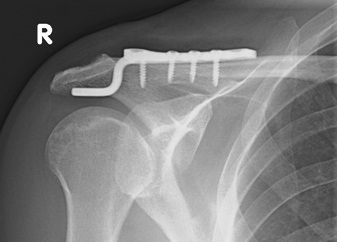

Die Hakenplatte Zur Operativen Behandlung Von Schultereckgelenksprengungen